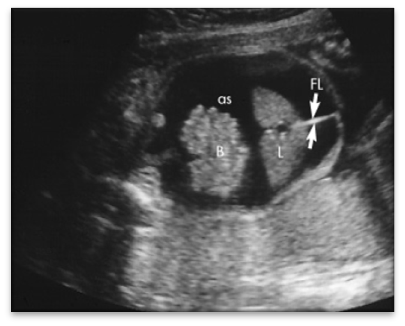

Nephroma / Hydro

Nephroma